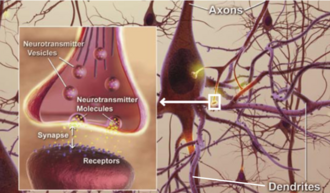

Alzheimer’s Dementia is the most common form of dementia, accounting for 60-80% of all dementia cases worldwide. While many people think of it simply as “memory loss,” Alzheimer’s Dementia is actually a complex brain disorder that affects thinking, behavior, and the ability to perform everyday activities. The disease develops when abnormal protein deposits, amyloid plaques, and tangles build up in the brain, disrupting communication between brain cells and eventually causing them to die. This process typically begins years before symptoms become noticeable, which is why early detection and understanding of Alzheimer’s Dementia is so crucial for families.

Yet even in this stage, connection remains possible. Alzheimer’s Dementia may take away words, but it doesn’t eliminate the capacity for emotional connection. A gentle touch, familiar music, or simply your loving presence can still provide comfort and peace.

While there’s currently no cure for Alzheimer’s Dementia, several treatment options can help manage symptoms and potentially slow progression. Medications like cholinesterase inhibitors and memantine can help with cognitive symptoms in some people.

Non-drug approaches are equally important in Alzheimer’s Dementia care. Regular physical exercise, social engagement, cognitive stimulation, and maintaining good overall health can all contribute to a better quality of life. Music therapy, art therapy, and pet therapy have shown particular promise in helping people with Alzheimer’s Dementia maintain emotional connections and express themselves. Research into Alzheimer’s Dementia continues advancing, with scientists exploring everything from new medications to lifestyle interventions that might prevent or delay the onset of symptoms. While we wait for breakthrough treatments, focusing on quality of life and meaningful connection remains the most important gift we can give our loved ones.